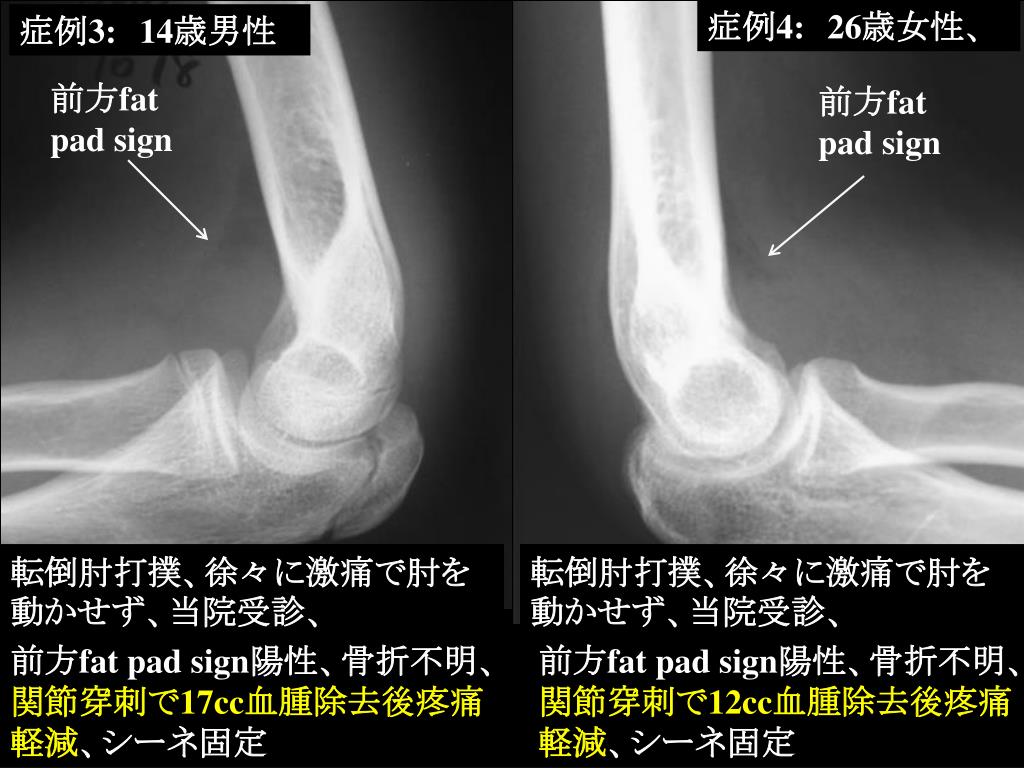

11. 症例4:26歳女性、 症例3:14歳男性 前方fat pad sign 前方fat pad sign 転倒肘打撲、徐々に激痛で肘を動かせず、当院受診、 転倒肘打撲、徐々に激痛で肘を動かせず、当院受診、 前方fat pad sign陽性、骨折不明、関節穿刺で17cc血腫除去後疼痛軽減、シーネ固定 前方fat pad sign陽性、骨折不明、関節穿刺で12cc血腫除去後疼痛軽減、シーネ固定